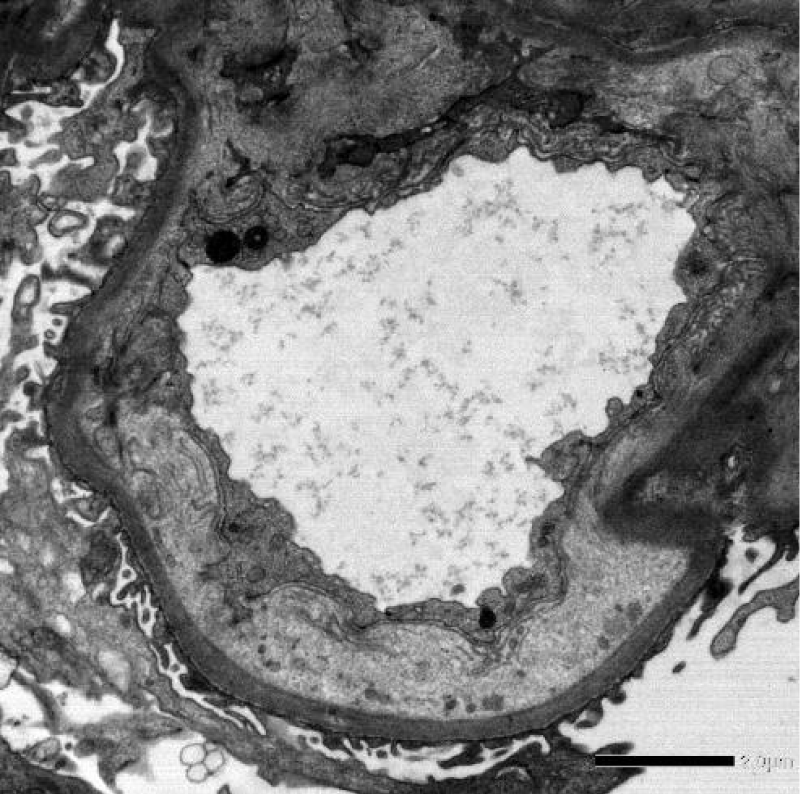

A 69-year-old male with urothelial carcinoma developed hypertension and Acute Kidney Injury (AKI) three months after initiating nivolumab, an anti-PD1 antibody. Urine analysis revealed nephrotic-range proteinuria, confirmed by a 24-hour urine protein-creatinine ratio, and worsening serum creatinine (Figure 1). A renal biopsy was performed, revealing global glomerulosclerosis in five out of six glomeruli, along with focal subcapsular collagen, periglomerular fibrosis, and one segmentally sclerosed tuft. Immunofluorescence showed negative results for IgA, IgG, C1q, kappa, and lambda light chains, while IgM and C3 were segmentally positive (2+ and 1+, respectively). Electron microscopy identified effacement of visceral epithelial cell foot processes (60%), severe active and chronic endothelial injury, prominent, diffuse GBM subendothelial widening, and no immune complex type electron-dense deposits (Figures 2,3). The diagnosis was Focal Segmental Glomerulosclerosis (FSGS) secondary to vascular endothelial disorder and podocyte damage, likely induced by nivolumab. Despite discontinuing nivolumab, his renal function remained compromised [1-5].

Figure 2: Electron microscopy (EM) illustrating podocyte effacement.

Figure 3: Electron microscopy (EM) showing GBM subendothelial widening.